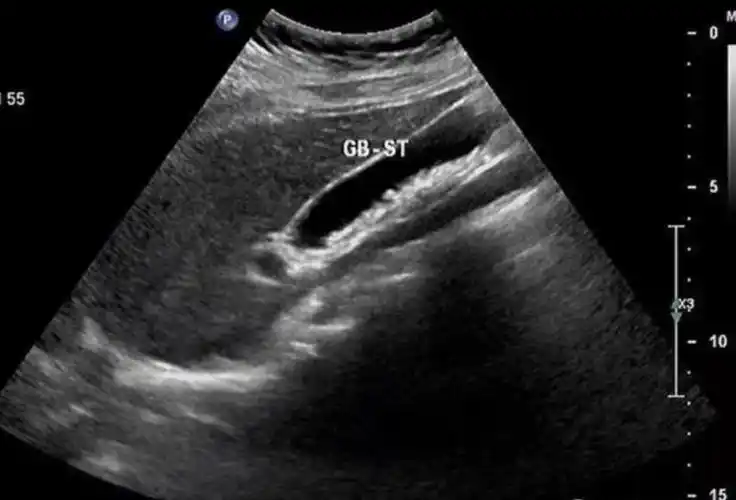

胆囊结石,超声表现是这样的

胆囊结石,超声这样表现